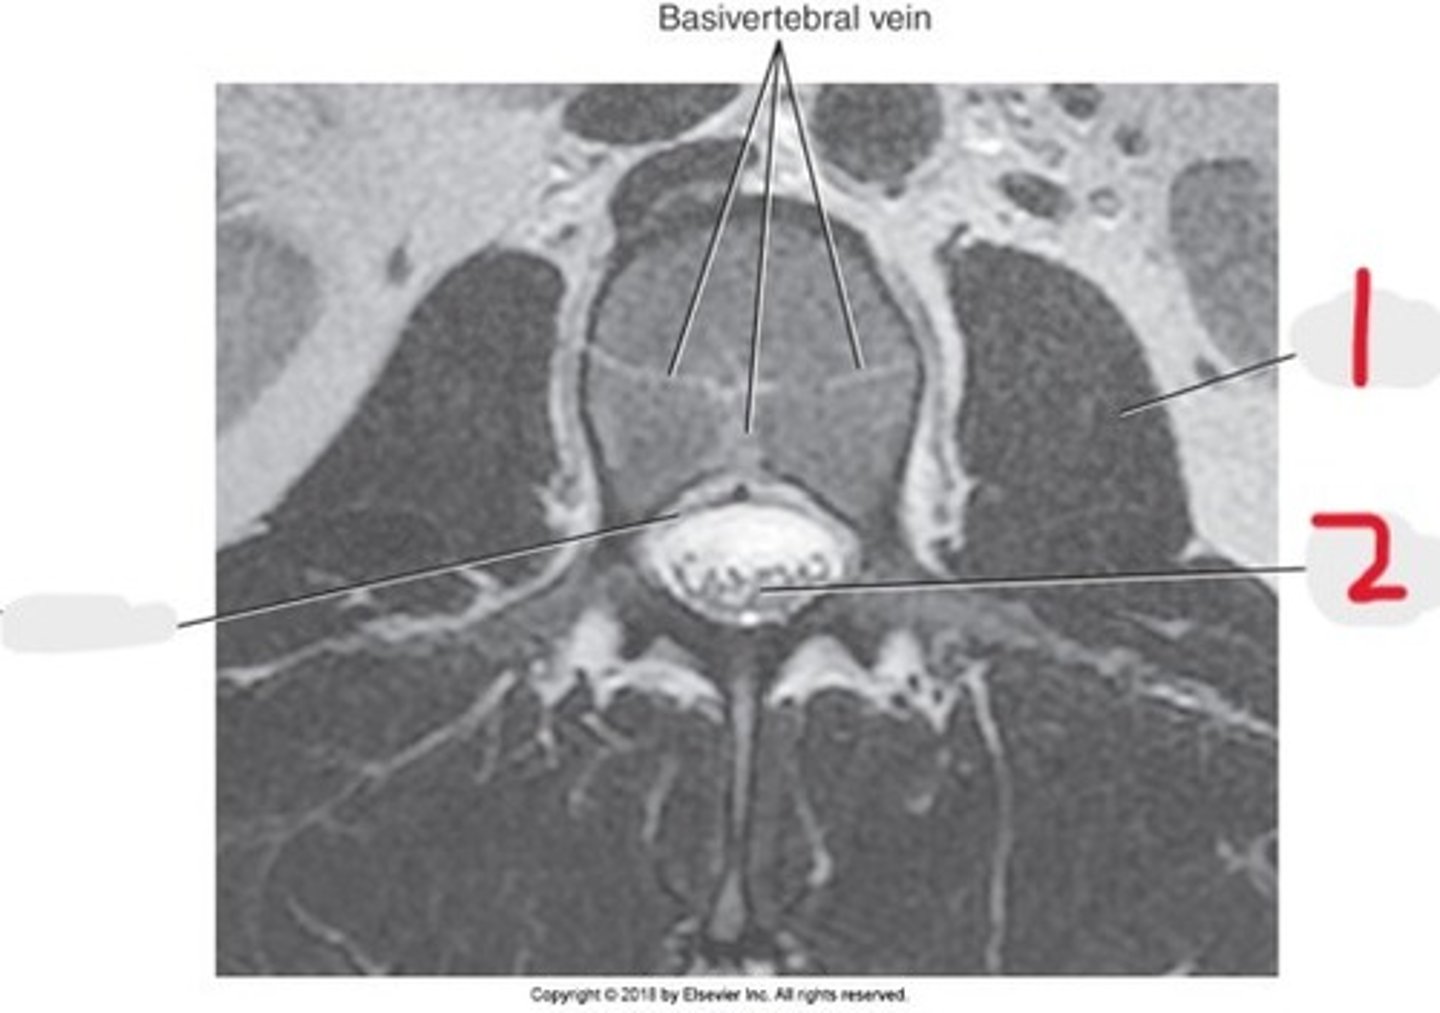

1) Psoas muscle

2) Cauda equina

Name all numbered structures

1) Psoas muscle

2) Vertebral body

3) Cauda equina

Name all numbered structures